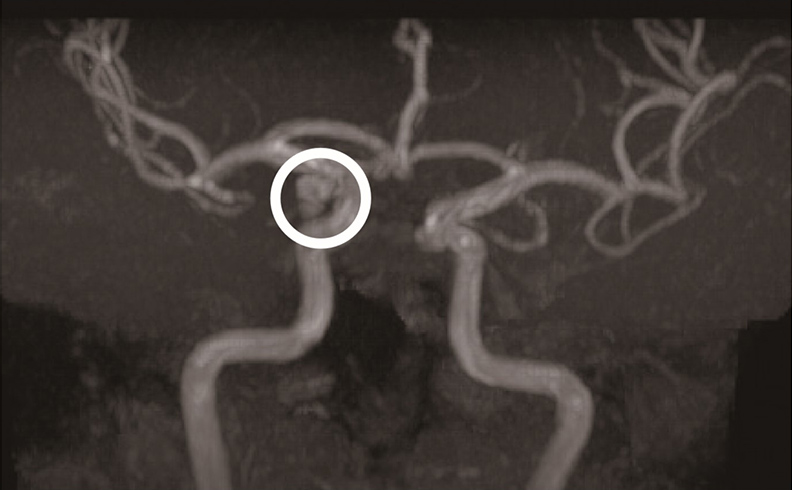

動脈瘤大多位於顱內動脈主幹的分叉處,呈草莓狀或囊狀,形成的原因主要是先天性的肌肉層缺損。蜘蛛網膜下腔出血多半是因該處動脈早已存在的動脈瘤破裂所致,破裂流出的血液在蜘蛛網膜下腔蔓延,出血越多,腦組織進一步受破壞的範圍就越大。由於血管的破裂是一瞬間的,因此,許多患者描述,破裂那一剎那,「頭就像被人用棍子狠狠地敲了一下」,或「一輩子從來沒經驗過那麼嚴重的頭痛,像爆炸一般」,由此可見,這種劇烈的頭痛不是在數秒或數分鐘內慢慢出現的,而是瞬間即達疼痛高峰。

蜘蛛網膜下腔出血是死亡率很高的危險疾病。若是第一次動脈瘤破裂,死亡率約1/3;第二次出血,死亡率增為2/3;若是第三度出血,死亡率幾達百分之百。若電腦斷層看不見蜘蛛網膜下腔出血,須與中樞神經感染(如腦膜炎)鑑別診斷時,便需要進行腰椎穿刺檢查確立診斷。其次,也需要做腦血管攝影來確定診斷動脈瘤。